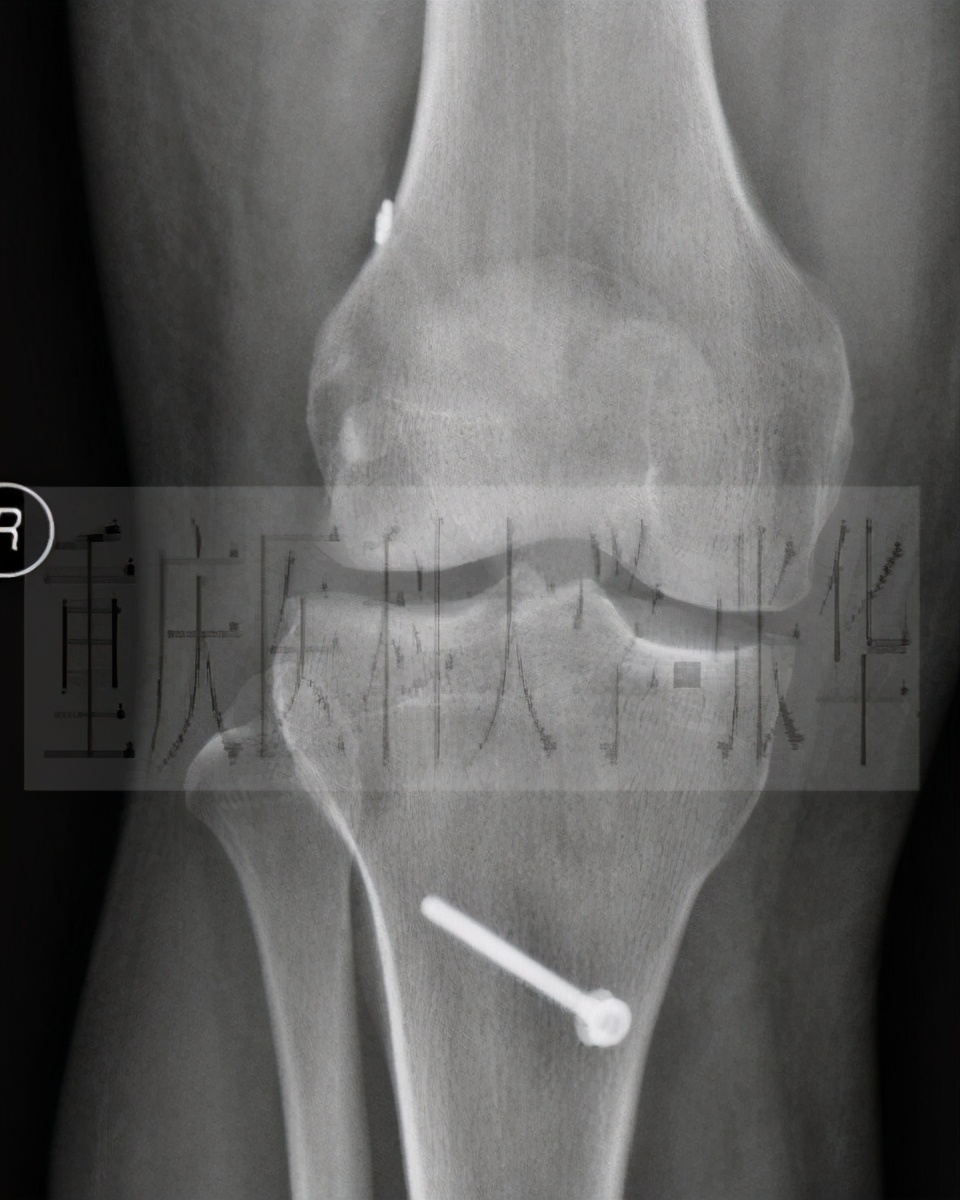

前交叉韧带 单束 重建术后的X片

前交叉韧带 双束 重建术后的X片